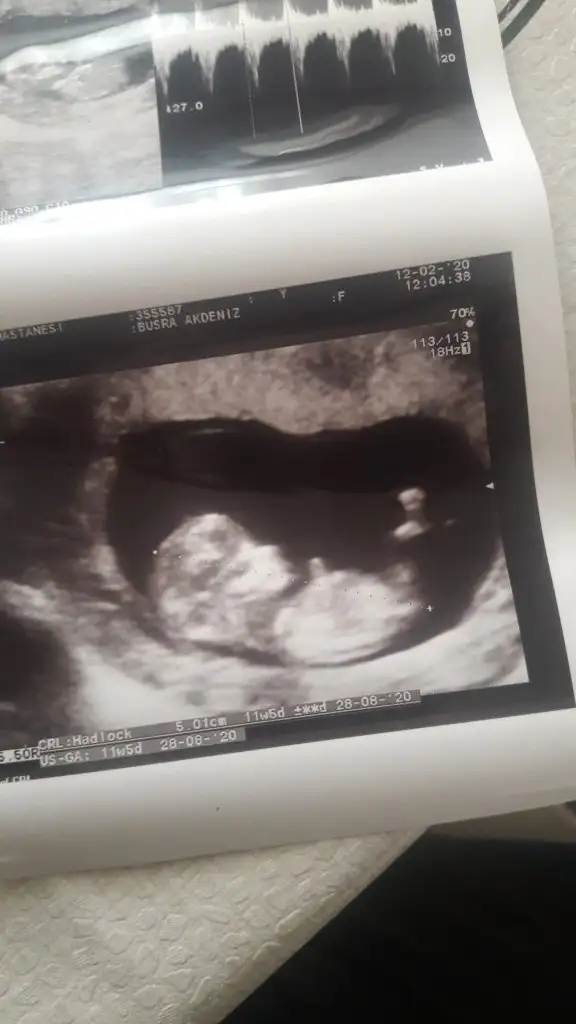

dr soylemeden siz gorun genital nub teorisi ( bebegin cinsiyeti)

Ikra meyra Ikra meyra merhaba canım banada yardımcı olur musun cok merak edıyorum